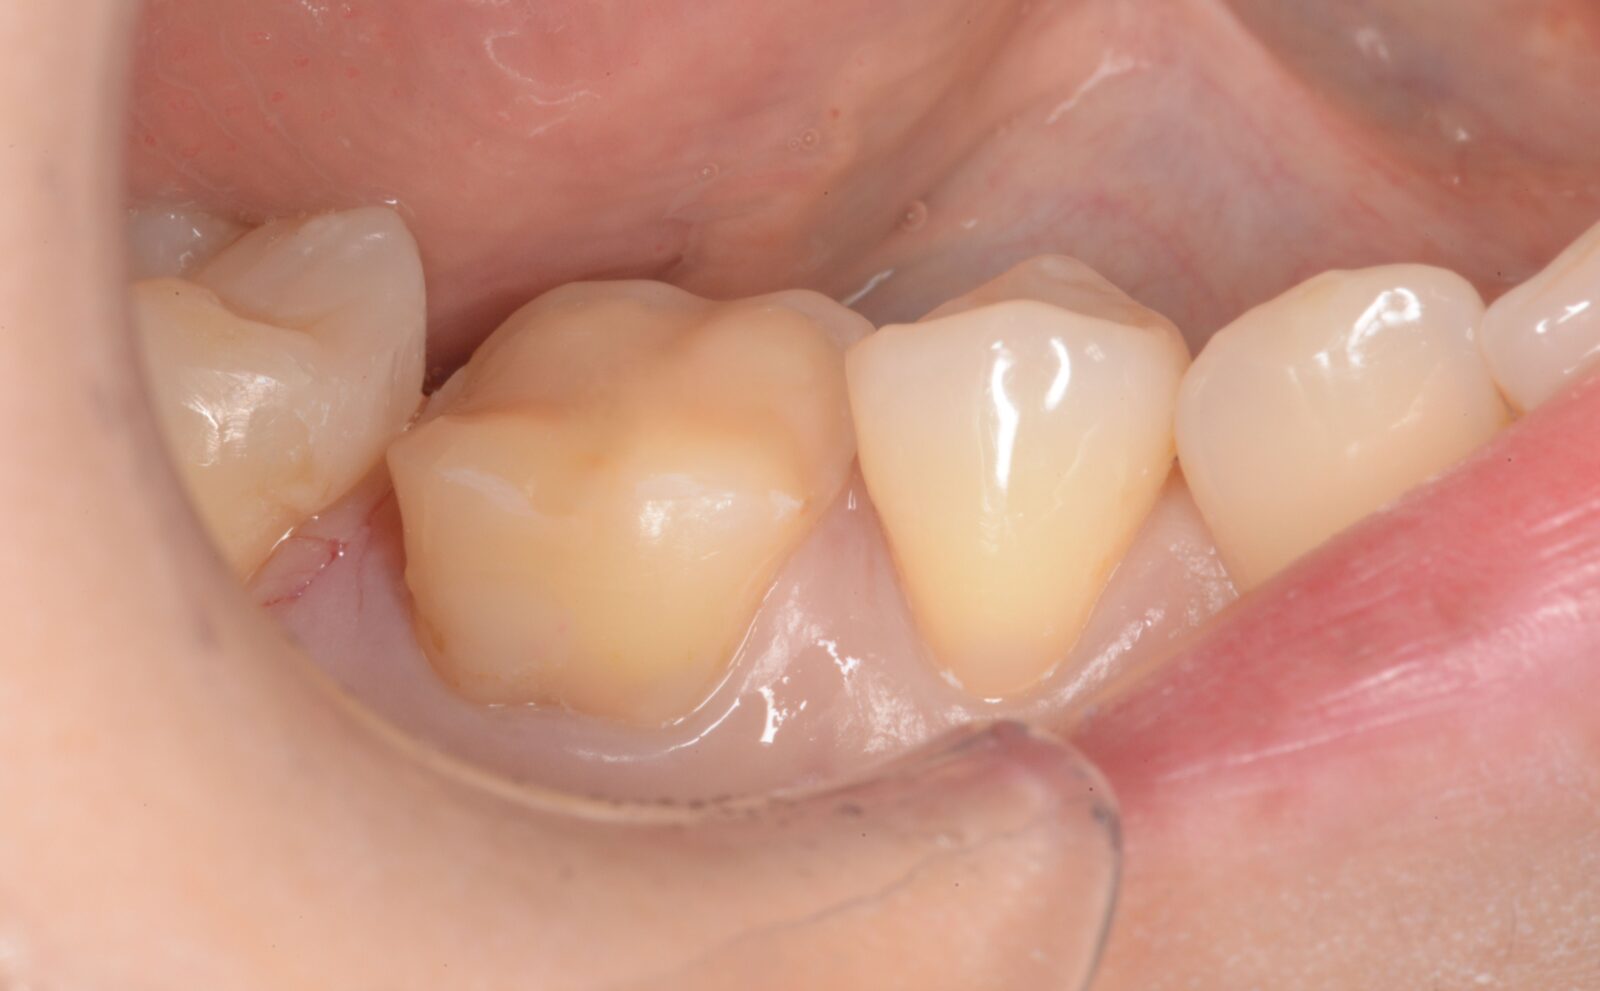

治療前 治療後

左上6,7ダイレクトボンディング

左上6➡他院で治療したセラミックスの接着不良からの二次感染。 左上7➡コンポジットレジンの接着不良からの二次感染。   ともに、旧充填物と感染歯質を除去後、歯面処理と接着操作を行う。 その後、ダイレクトボンディングにて、充填処置を行い、ティント(ブラウンとホワイト)…